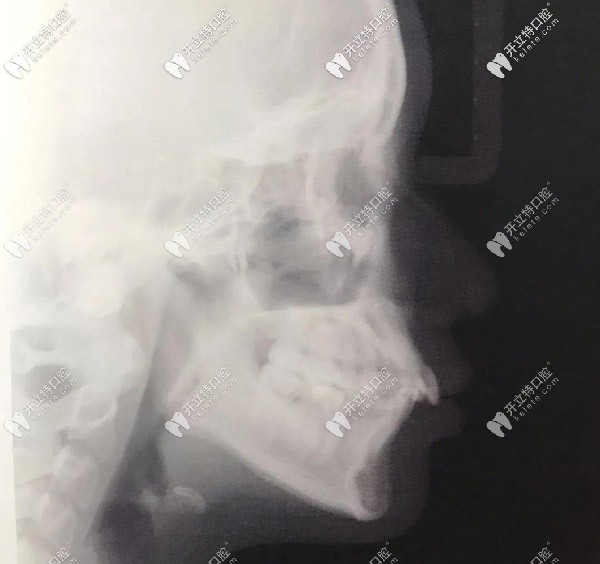

側(cè)面X光,門(mén)牙唇傾很厲害的

▲側(cè)面X光,門(mén)牙唇傾很厲害的